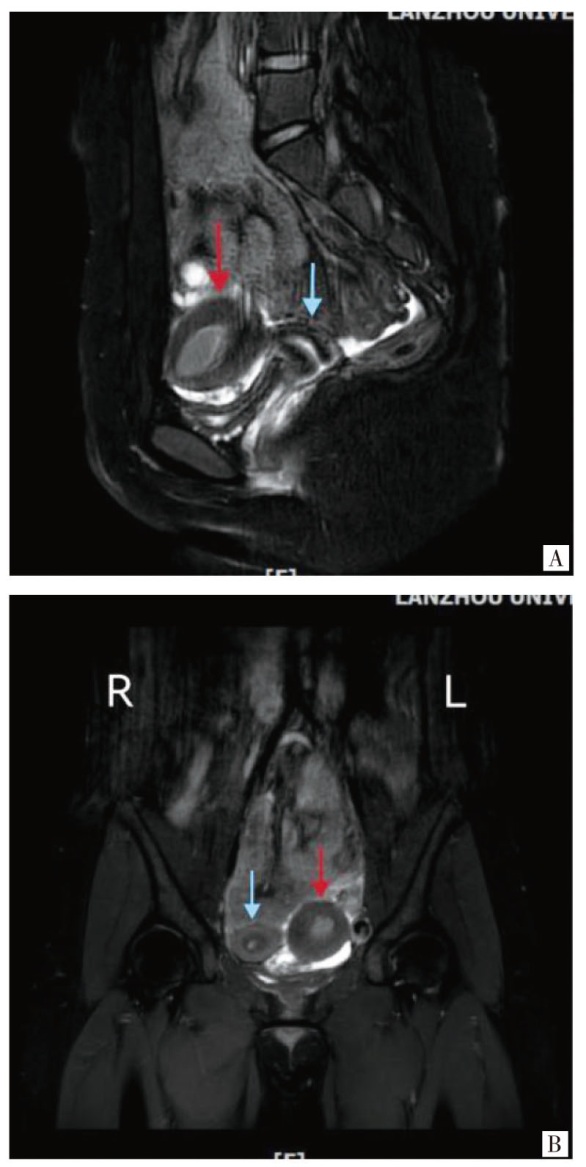

单角子宫作为米勒管发育异常的重要类型之一,是指仅有一侧米勒管正常发育而形成的子宫畸形。流行病学数据显示,该畸形占子宫畸形的 0.3%~4.0%,其中约35%的病例会合并残角子宫及同侧肾缺如。报告1例左侧非交通型有腔残角子宫合并同侧肾缺如青少年患者,临床表现为痛经并进行性加重,经盆腔磁共振成像检查确诊,排除手术相关禁忌证后行经脐单孔腹腔镜下残角子宫切除术+左侧输卵管切除术+盆腔子宫内膜异位病灶切除术+盆腔粘连松解术+脐整形术,术后病理证实残角子宫内膜呈分泌期改变,患者痛经症状缓解。提示早期诊断和规范化的手术治疗对改善患者生活质量具有重要意义。